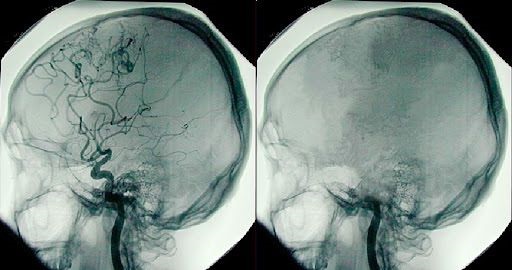

El doctor comprobó que Jahi tenía ausencia total de reflejos del tronco cerebral, un criterio esencial de muerte encefálica. A la vez, registró actividad cerebral organizada en el electroencefalograma (EEG), con amplitud superior

a 2 μV (microvoltio), incompatible con un electroencefalograma inactivo.

Cabe destacar que el profesor Machado no cuestiona la validez de la muerte encefálica. Al contrario, la ha defendido durante décadas. Su investigación muestra que existen casos extremadamente raros con patrones atípicos. En esas circunstancias, considera imprescindible aplicar pruebas confirmatorias obligatorias —EEG, estudios de perfusión cerebral y análisis neurofisiológicos profundos— antes de llegar a un diagnóstico definitivo. Lo cual implica reconocer que puede existir una lesión del tronco cerebral junto a funciones subcorticales residuales.